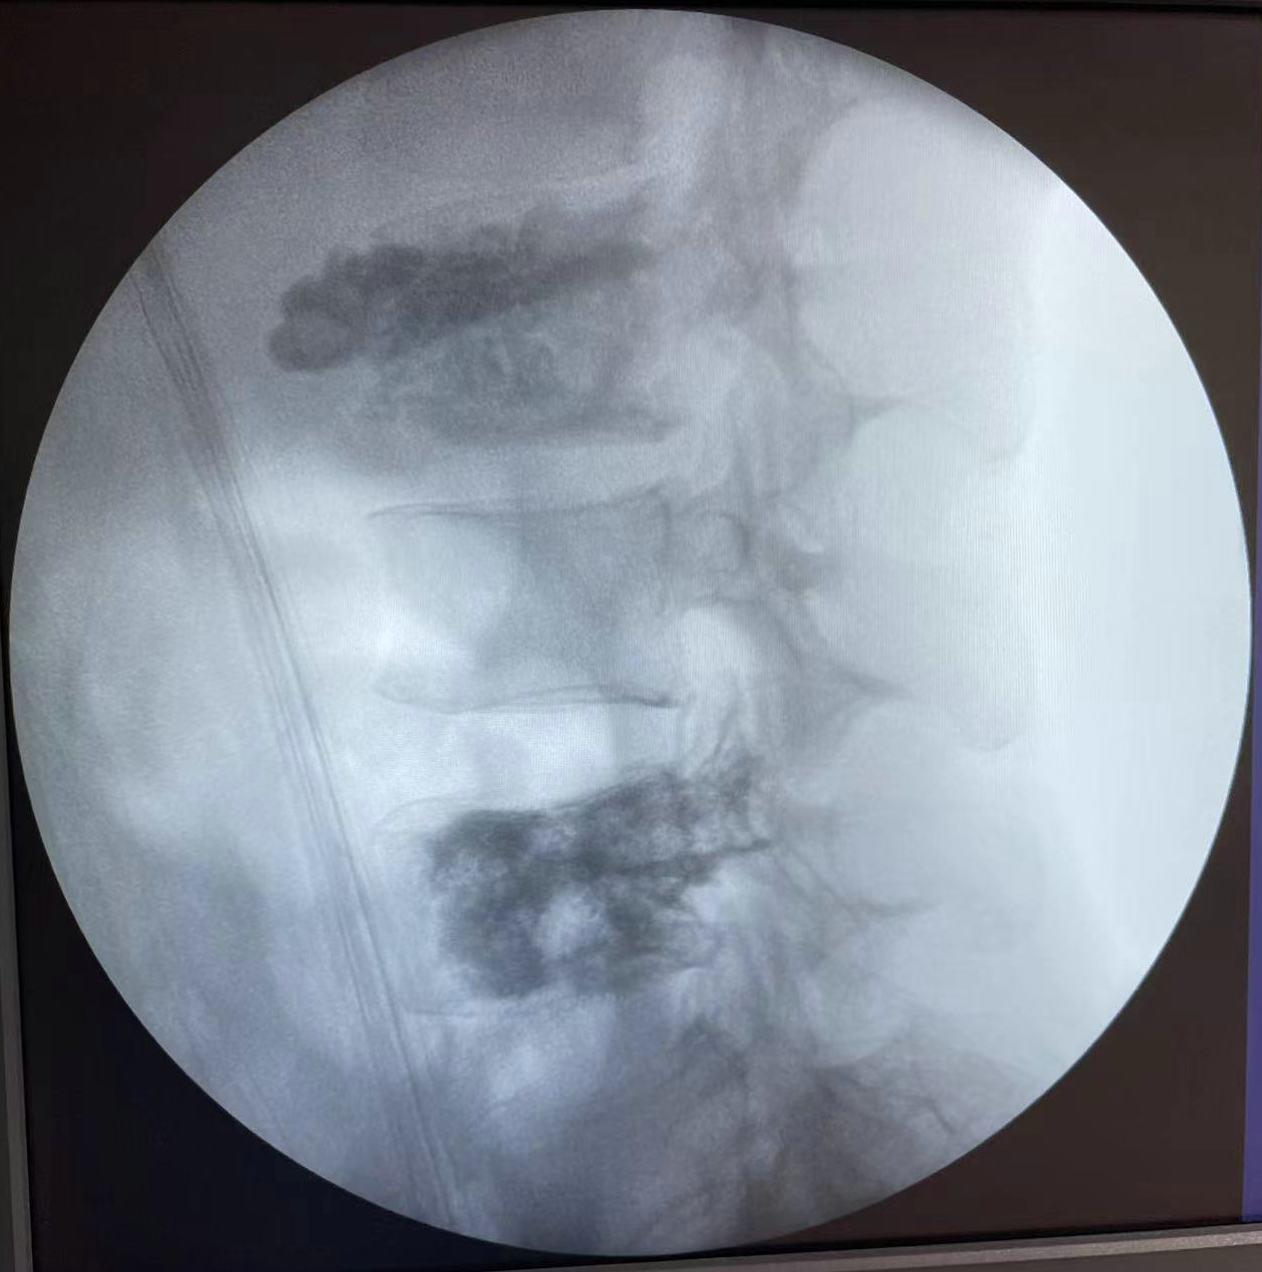

术后X线片